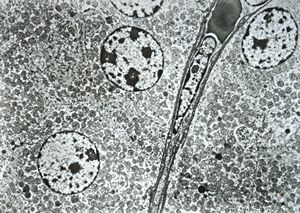

normal kidney - mouse(endothelium and podocytes)

normal kidney - mouse(endothelium and podocyte)